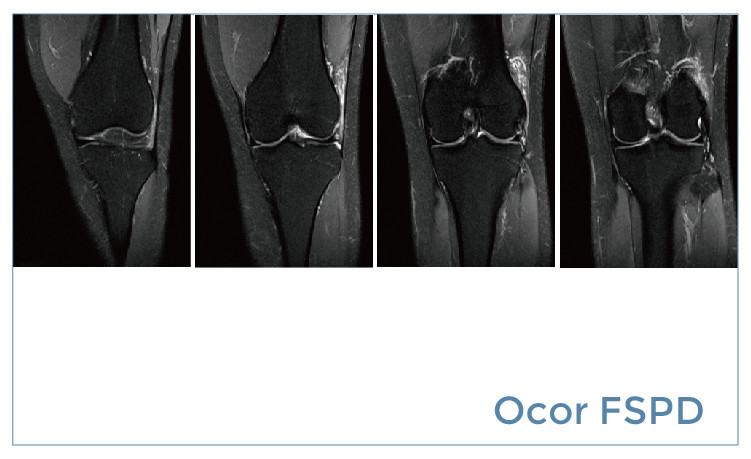

【朗润影像档案】磁共振影像病例分享(编号20190510)